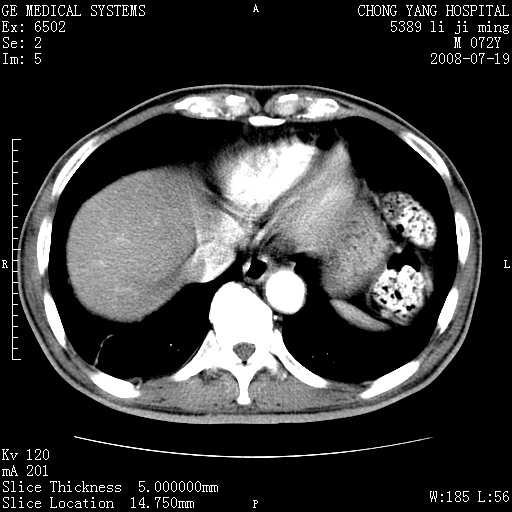

以下是引用zjzjr在2008-7-19 20:57:00的发言:[br]胰头增大,边缘模糊,周围可见渗出影,右侧肾前筋膜增厚.支持胰腺炎.

以下是引用不学无术在2008-7-19 23:15:00的发言:[br]胰腺增大尤以胰头明显,边缘模糊,周围可见渗出影,右侧肾前筋膜增厚,肠管於涨.支持胰腺炎